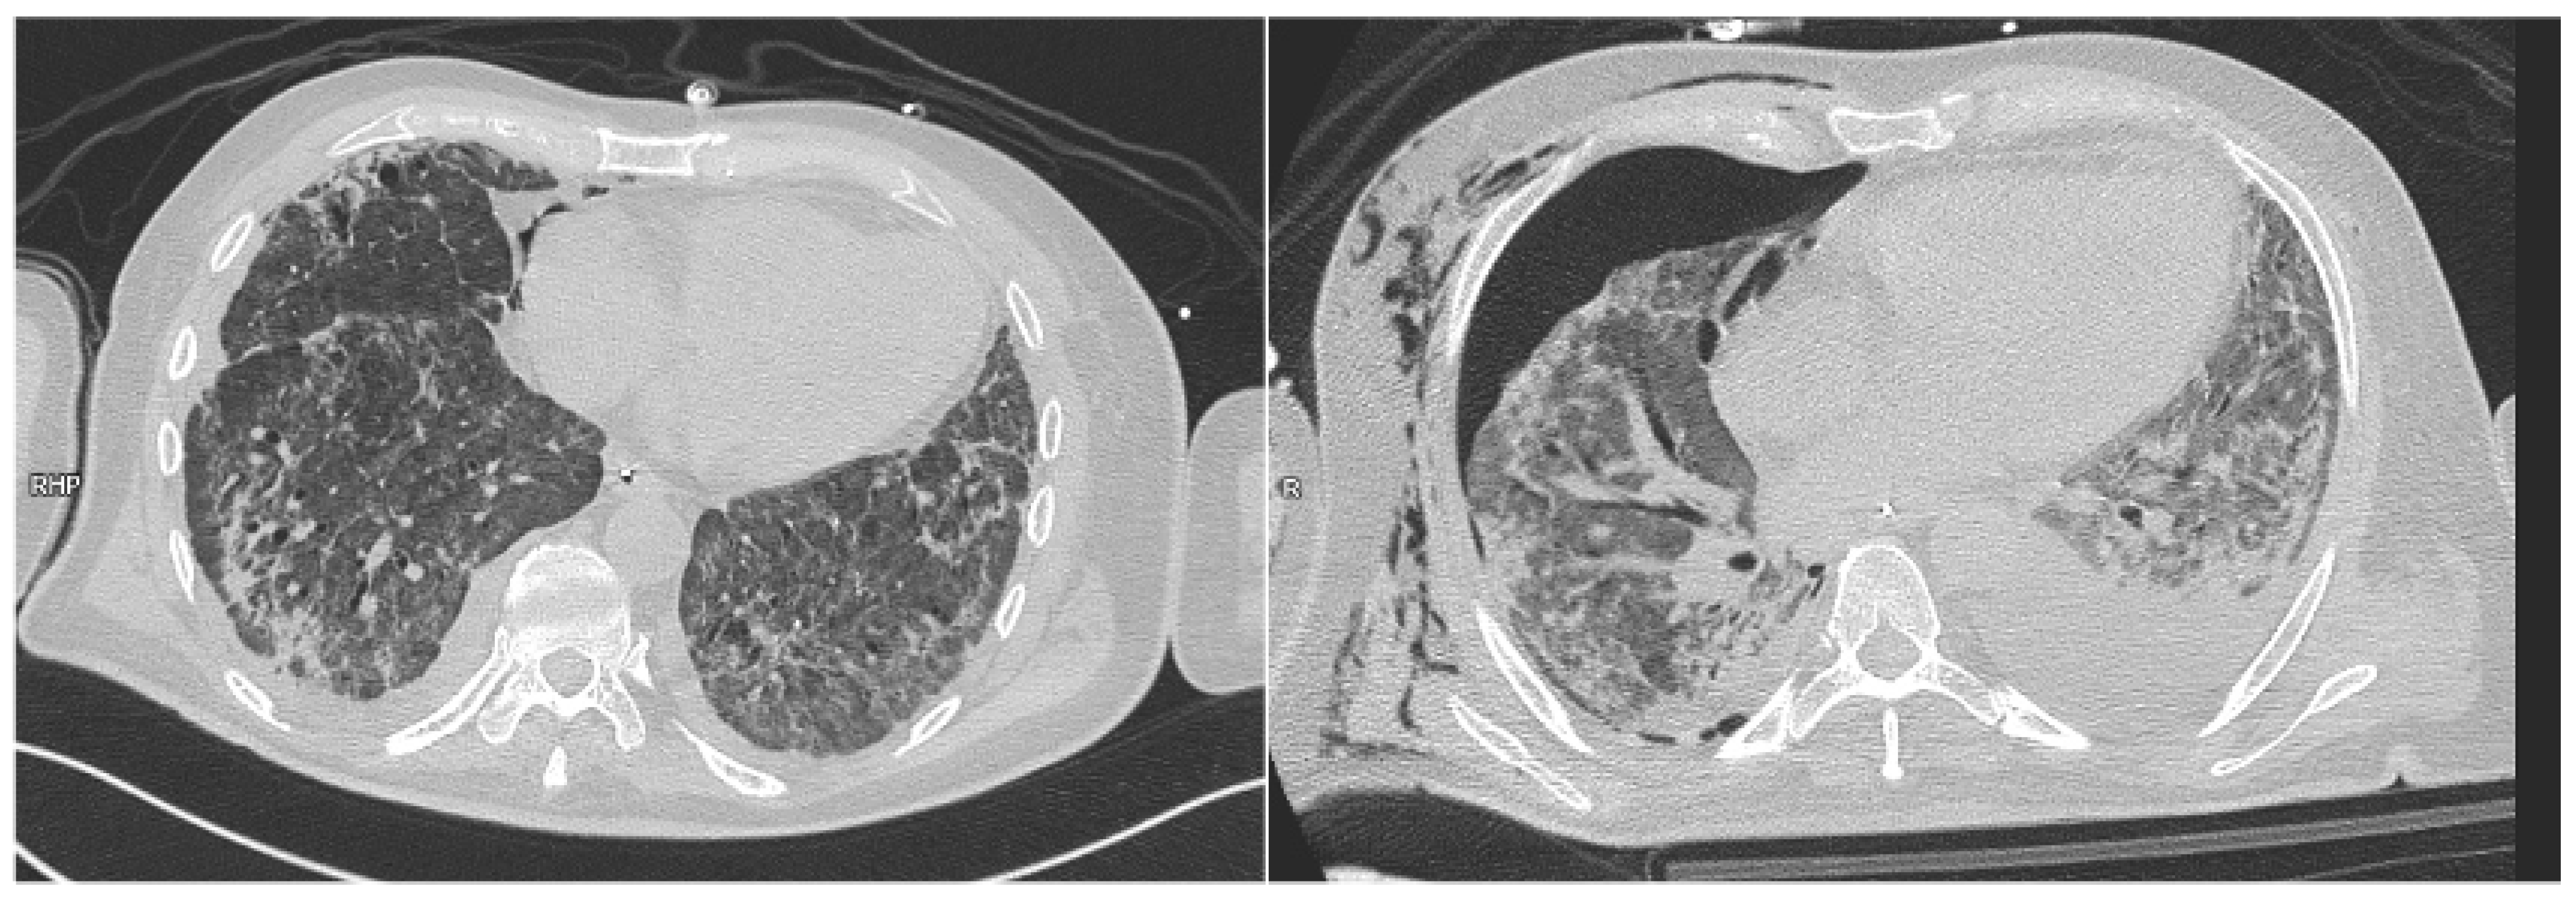

- Paternoster, G.; Belmonte, G.; Scarano, E.; Rotondo, P.; Palumbo, D.; Belletti, A.; Corradi, F.; Bertini, P.; Landoni, G.; Guarracino, F.; et al. Macklin Effect on Baseline Chest CT Scan Accurately Predicts Barotrauma in COVID-19 Patients. Respir. Med. 2022, 197, 106853. [Google Scholar] [CrossRef] [PubMed]